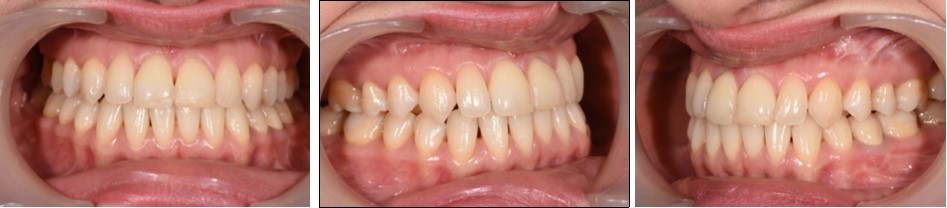

Intraoral examination revealed bilateral Angle’s class III molar relationship, class III canine relationship on the right and class I on the left, a deviated lower dental midline to the left of the patient, a visible negative tip in the right upper lateral incisor and canine, crossbite between 1.2. and 4.3 and 4.4, retroclined lower incisors, proclined upper incisors, with a 1 mm overbite and overjet . (Figure 2)

Figure 2.Initial intraoral photographs

Initial intraoral photographs